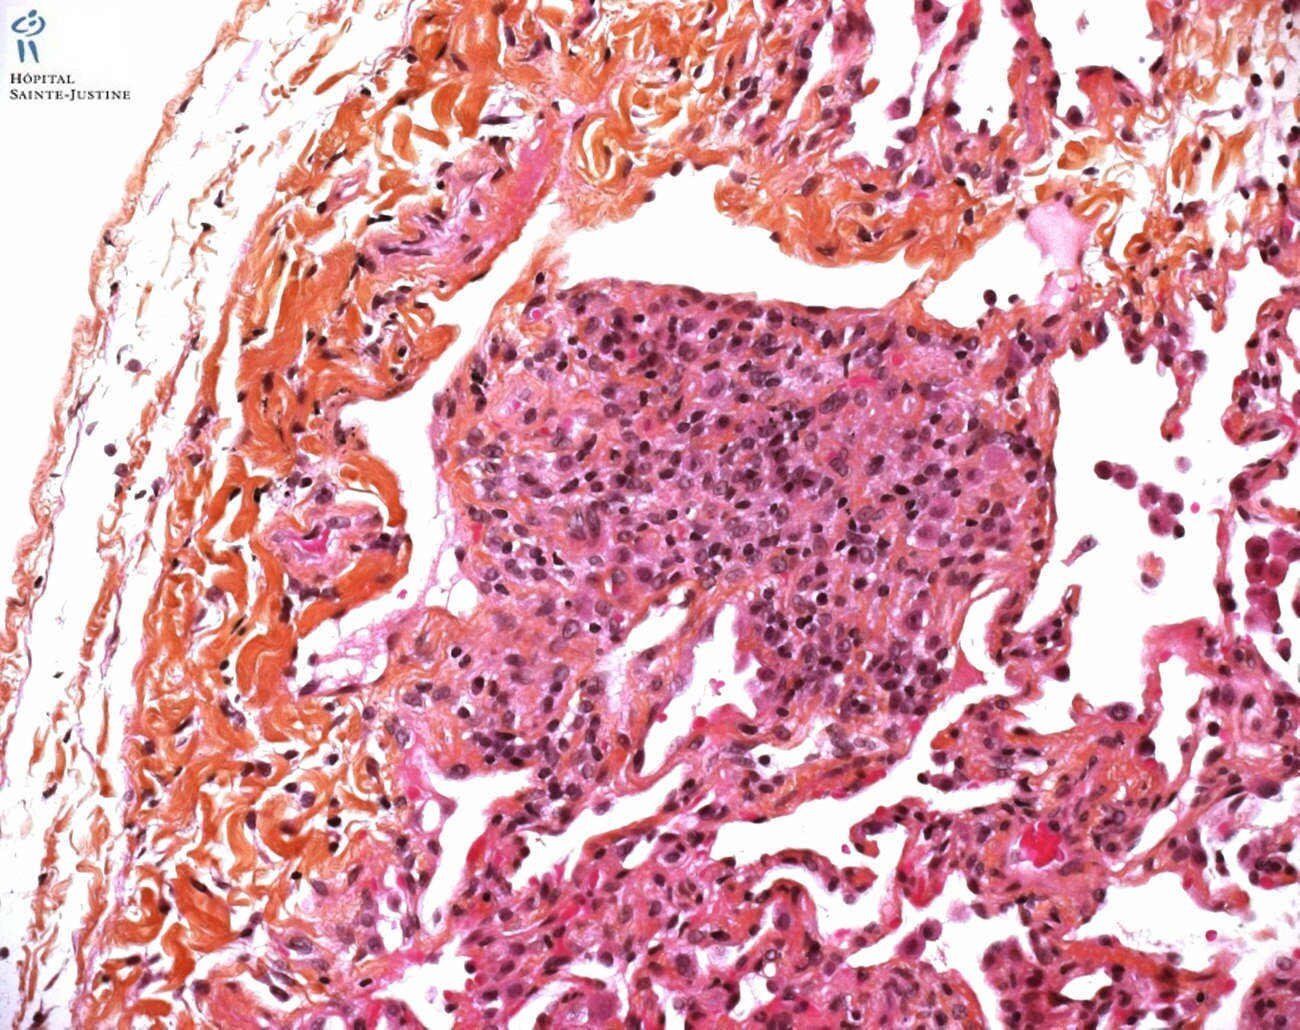

necrotizing bronchiolitis